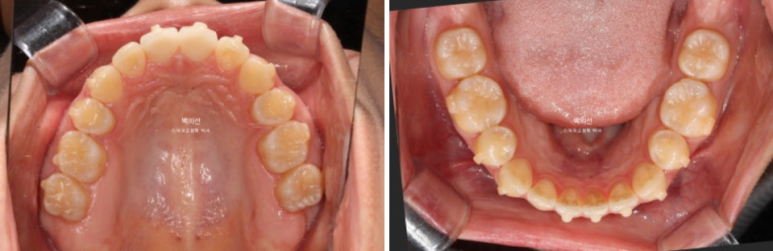

25.02~25.07

이제 전후 비교 보겠습니다.

총 치료기간은 4개월입니다.

25.02~25.06

어금니교합 뿐만 아니라 앞니 교합까지 더 긴밀해졌습니다.

남은 공간이 사라지며 윗니 돌출이 개선되었습니다.

뼈속에서 붙어있던 송곳니와 작은어금니 뿌리들은 4개월의 교정으로 비로소 서로 멀어지며 정렬을 찾았습니다.